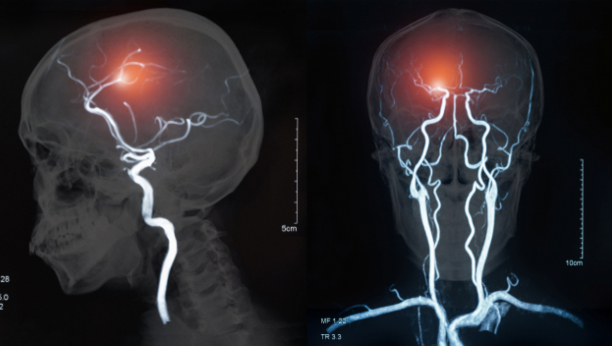

Tokom dijagnostičkog pregleda, otkrivene su brojne ciste na obema polutkama mozga i otok. Stručnjaci za infektivne bolesti utvrdili su da je uzrok upale svinjska pantljičara koja je unutar njegovog mozga položila jaja, iritirajući tkivo ispod lobanje. Smatra se da je infekcija nastala nakon konzumiranja nedovoljno pečene slanine, a pacijent je priznao da preferira mekšu slaninu.

Naglasio je da nije nedavno putovao van zemlje niti jeo sirovu hranu. CT i MRI snimci otkrili su mnogobrojne ciste na obema stranama mozga. Dijagnoza je bila neurocisticerkoza, parazitska infekcija.

Ovo stanje opisuje situaciju kada larvalne ciste svinjske pantljičare, koje su zatvorene kese sa nezrelim fazama parazita, inficiraju različite delove tela, izazivajući upalu.